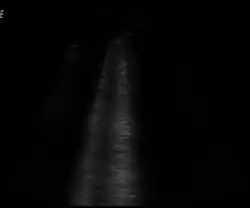

An ultrasound image showing early pulmonary contusion, at this moment not visible on radiography. Lung swelling is seen as vertical white lines, the "B-lines".[53]

Pulmonary ultrasound, performed at the bedside or on the accident scene, is being explored as a diagnosis for pulmonary contusion. Its use is still not widespread, being limited to facilities which are comfortable with its use for other applications, like pneumothorax, airway management, and hemothorax. Accuracy has been found to be comparable to CT scanning.[54]